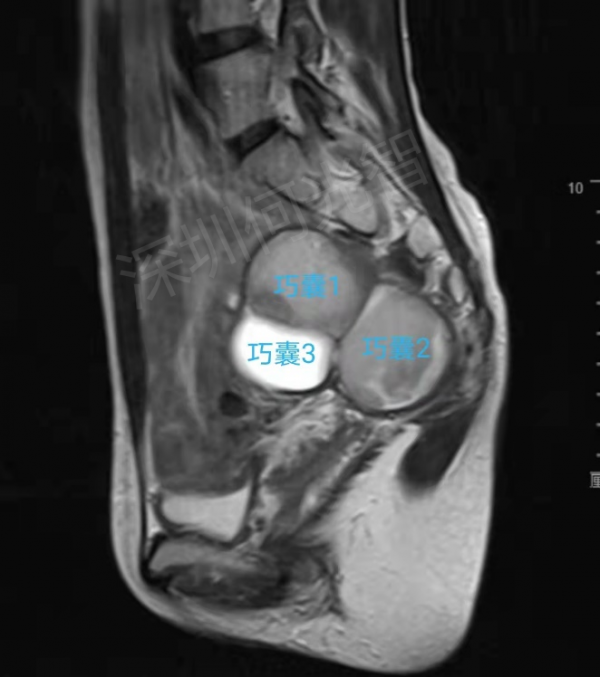

按照預約時間,孟小姐來到了何光智主任所在的介入超聲專家門診。透過詳細詢問病史,查閱過往檢查結果,現場超聲檢查,確認了右側附件區有三個囊腫,其中靠近深部的兩個囊腫(巧囊1與巧囊2),大小分別為55×52×46mm(超聲估測70mL)、36×34×35mm(超聲估測22mL),靠近淺部的一個大小為33×32×27mm(超聲估測14mL),確實需要治療。

鑑於孟小姐未婚未育,超聲介入硬化治療是理想的治療方案,但目前只有經腹穿刺的途徑可供選擇,然而囊腫位於盆腔深處,前方有腸管、子宮及膀胱阻擋,直接穿刺變為不可能。聽到這種情況,孟小姐才知道她的病情治療起來真是困難,之前在網上諮詢的專家並沒有錯,這種情況真的只有腔鏡手術一條路,可孟小姐擔心手術剝離囊腫對卵巢造成損傷,影響以後的生育,這下她又犯了愁。

術前磁共振提示右側附件區多發囊性佔位,考慮巧克力囊腫。囊腫被前方的腸管遮擋,經腹穿刺路徑受阻。